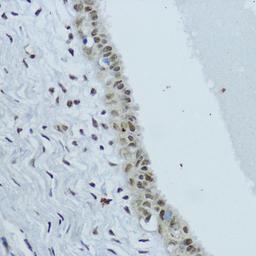

NR1I3 Rabbit pAb

- Primary Antibody

- Polyclonal

- Host

- Reactivity: Human, Mouse, Rat